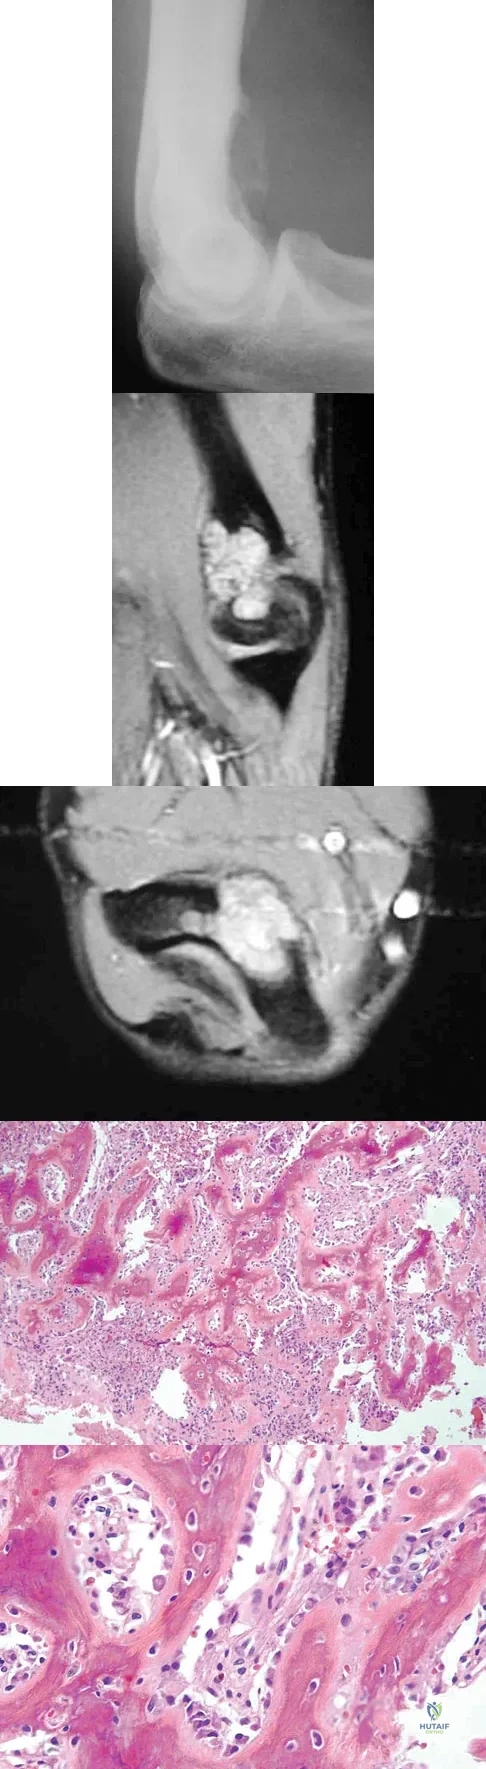

Question 4

A 17-year-old boy has had elbow pain for the past 6 weeks. A radiograph, MRI scans, and biopsy specimens are shown in Figures 65a through 65e. What is the most likely diagnosis?

Explanation